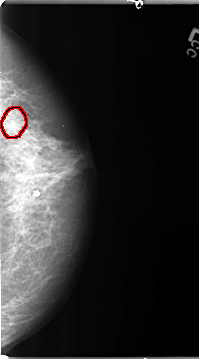

B_3094_1.LEFT_MLO

LEFT_CC LINES 4664 PIXELS_PER_LINE 2584 BITS_PER_PIXEL 12 RESOLUTION 50 OVERLAY

LEFT_MLO LINES 4680 PIXELS_PER_LINE 2752 BITS_PER_PIXEL 12 RESOLUTION 50 OVERLAY

FILE: B_3094_1.LEFT_MLO.OVERLAY

TOTAL_ABNORMALITIES 1

ABNORMALITY 1

LESION_TYPE CALCIFICATION TYPE PLEOMORPHIC DISTRIBUTION CLUSTERED

ASSESSMENT 4

SUBTLETY 4

PATHOLOGY BENIGN

TOTAL_OUTLINES 1

BOUNDARY